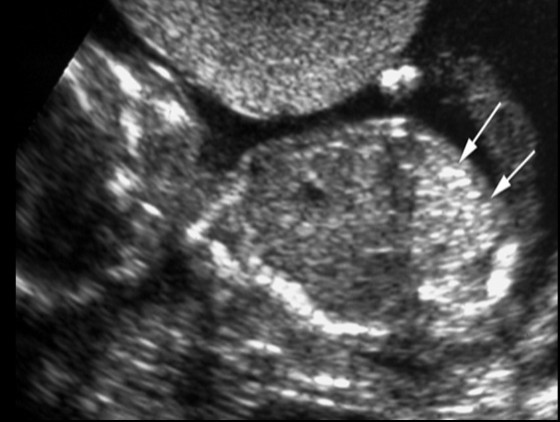

a pt has recent acute onset HTN, nausea, vomit. she has no pain, cramping, or vaginal bleeding. a prior US at 6w indicates the pregnancy should now be 17w6d GA. the image shows strong suspicion of

.

video is of trophoblastic gestation/molar - most fetuses have asymmetrical large head + small body

a) trisomy 21

b) triploidy

c) trisomy 13

d) trisomy 18